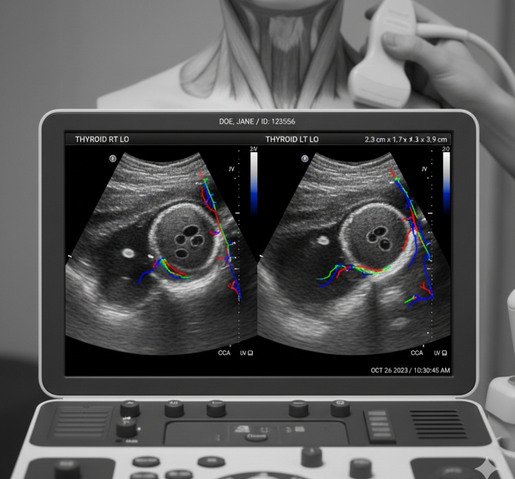

Ecografía Tiroidea

La ecografía tiroidea es un estudio no invasivo que permite evaluar la glándula tiroides, analizando su tamaño, forma, estructura y la presencia de nódulos u otras alteraciones. Es una herramienta fundamental para el diagnóstico, control y seguimiento de las enfermedades tiroideas.

En LUMA, la ecografía tiroidea es realizada por profesionales especialistas en diagnóstico por imágenes, utilizando equipos de última generación y alta definición, que permiten obtener imágenes precisas y confiables, contribuyendo a un diagnóstico certero.